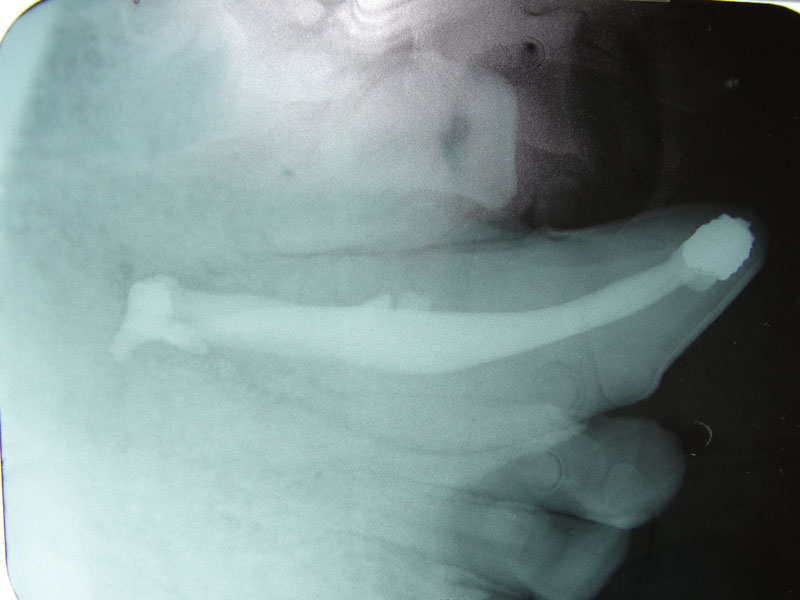

The open canal was prepared and the canal was debrided with endo files. It was irrigated with NaOCL and dried with paper points. A master cone was fitted, withdrawn and then ZOE base filler paste was deposited into the canal using the LVVES. The LVVES needle was placed at the apex and then withdrawn as the paste filled the canal. Then gutta percha was placed and condensed into the canal. When the canal was totally obturated a zinc phosphate cement base was placed over the fill. After the base set the opening was prepared with a no. 35, inverted cone bur. Then amalgam was placed and condensed.

The postoperative radiograph revealed a complete fill. Some overfill of the endo paste did flow into the chronic drainage tract.

The periapical lesion was debrided with small bone currettes. The exposed root apex was sectioned. Endodontic files were used to debride the entire root canal from the coronal end. Sodium hypochlorite and RC Prep (Root Canal Preparation©, Premier Dental Products, Co., 3600 Horizon Drive, King of Prussia, PA 19406-0974) was used to irrigate the canal during filing When the canal was prepared, irrigated, and dried, a PC pressure syringe (Pulpdent Corporation Pressure Syringe©, Pulpdent Corporation, 80 Oakland Street, Watertown, MA 02471, USA), was used to deposit the zinc oxide/eugenol paste until it extruded apically. Gutta percha points were fitted, placed and laterally condensed. A retentive preparation was made at the apical and coronal ends, and silver amalgam was used to seal the preparations. The surgical site was irrigated with sterile saline and closed with dissolving sutures.

lnteroperative and postoperative radiographs were obtained to verify endodontic working length and extent of endodontic fill.